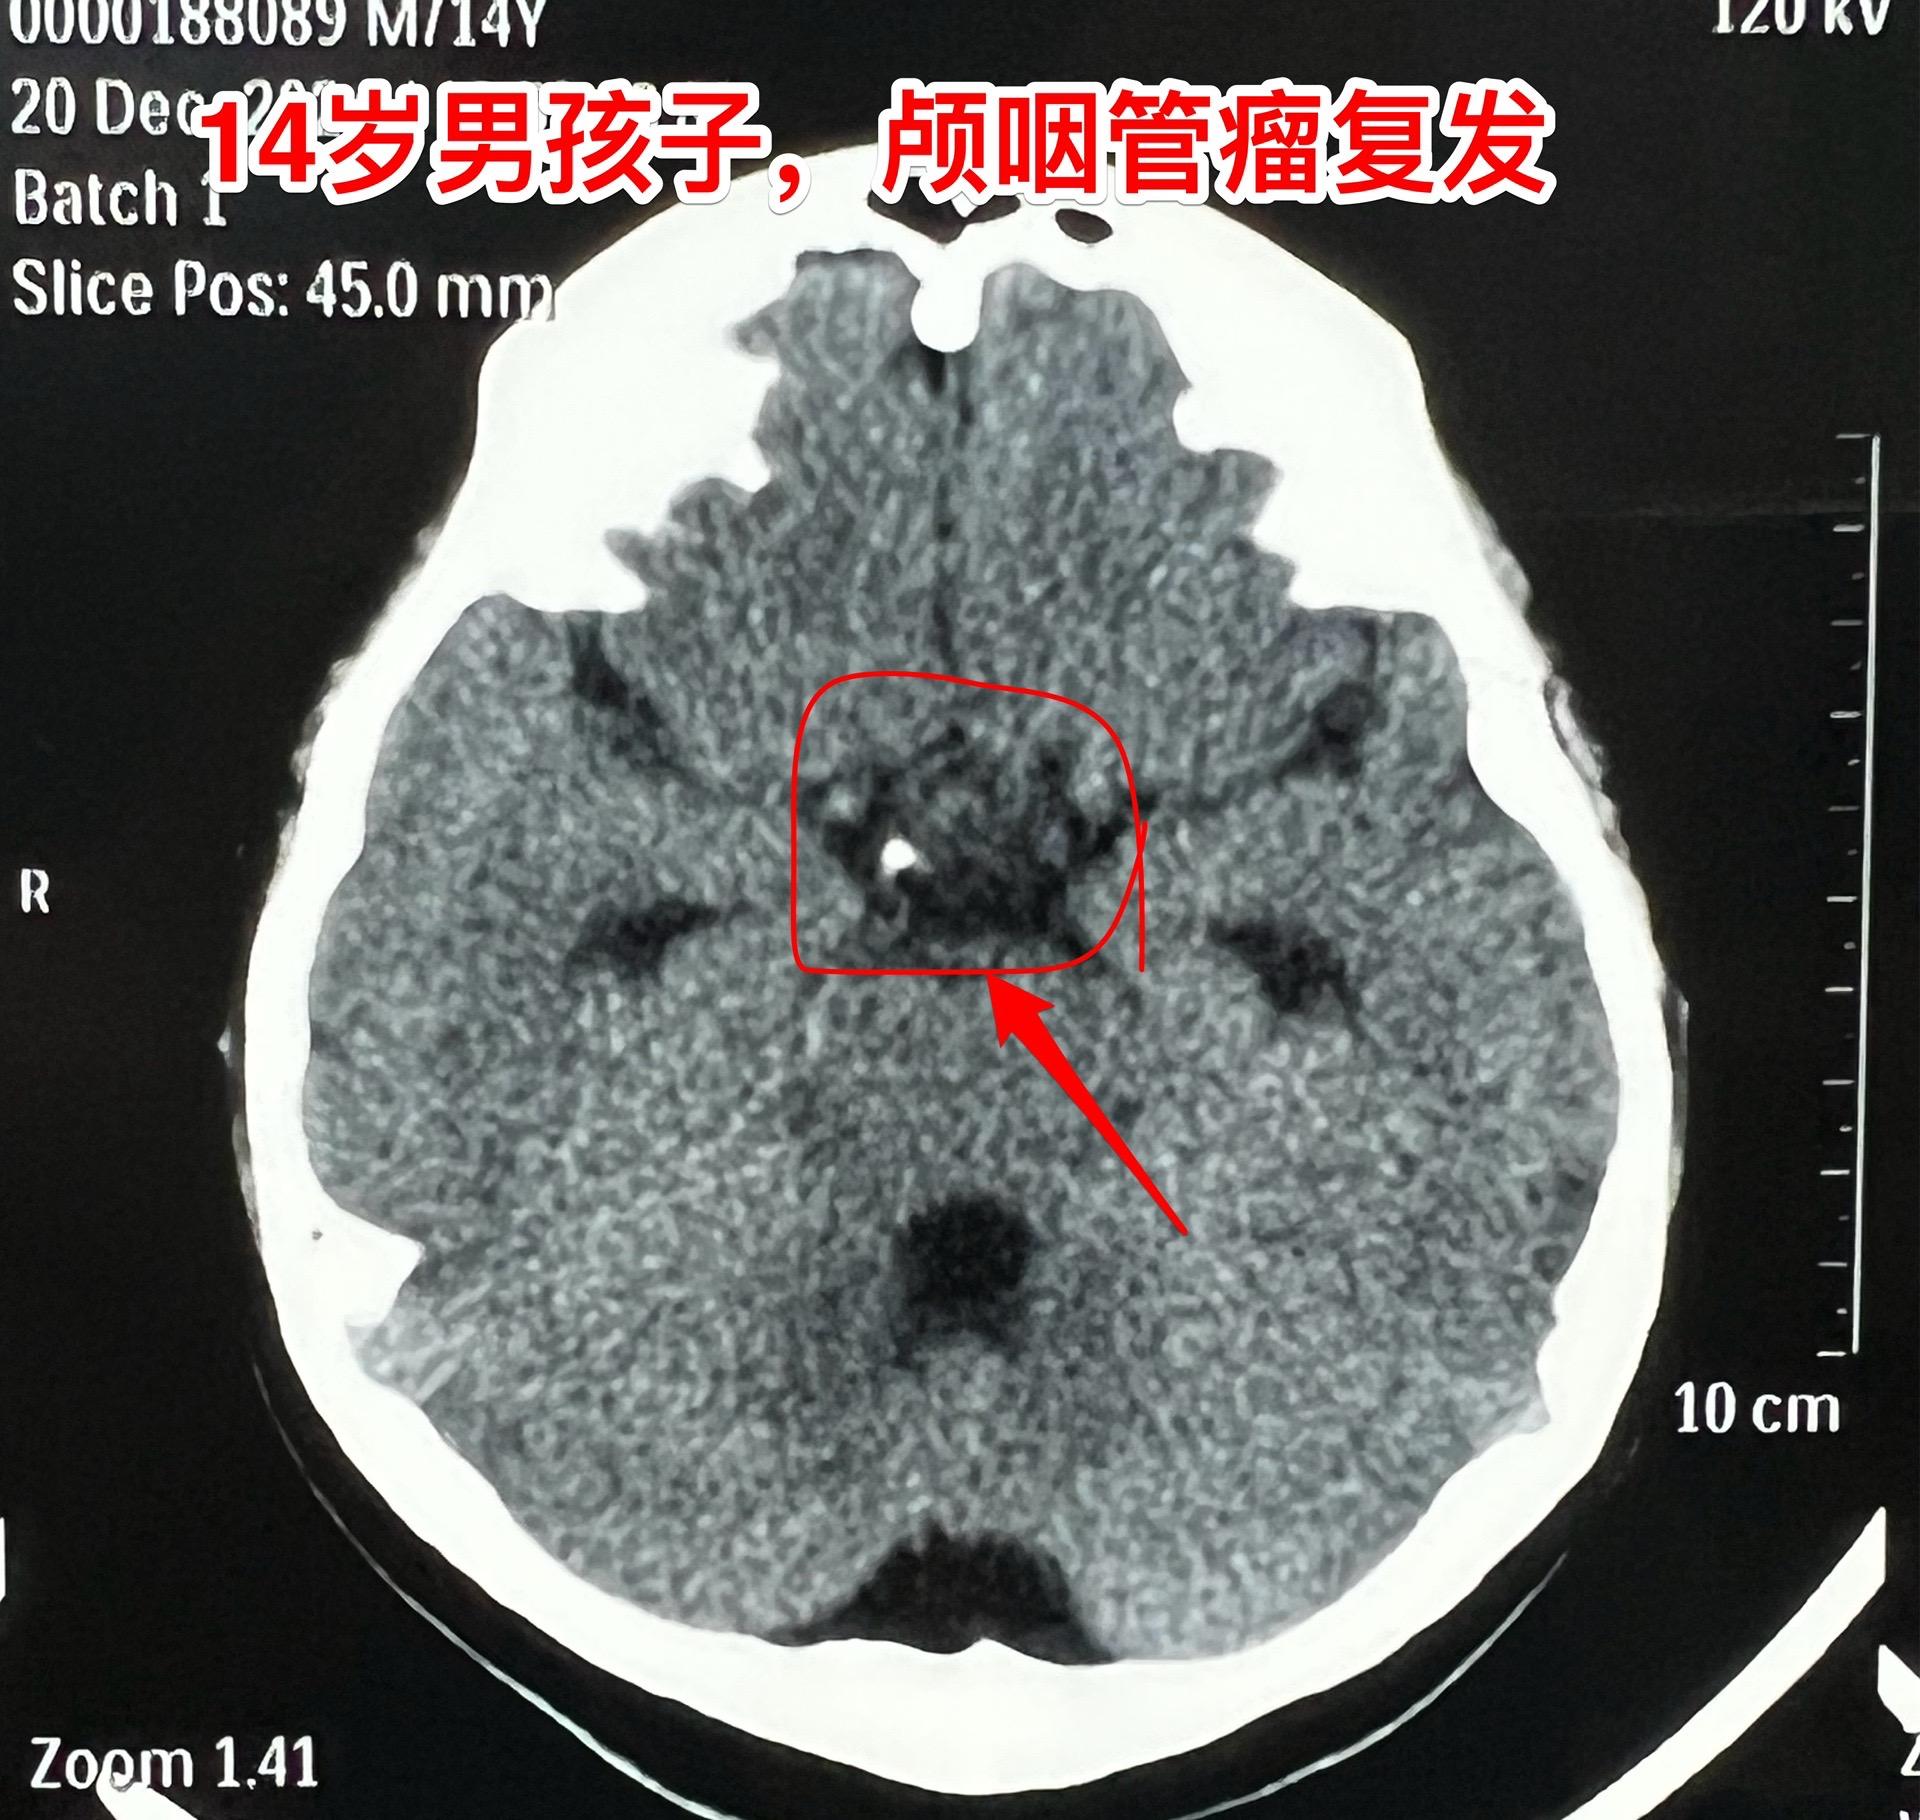

12月26日两个颅咽管瘤手术。第一个四岁男孩子,因为头部受伤,作CT发现颅咽管瘤。家长没有犹豫,选择尽快作手术。手术中将颅咽管瘤完全切除,垂体柄和垂体保留约50%。早作手术的好处就是肿瘤与周围结构粘连不紧密,易于分离,有助于完全切除肿瘤。 第二个病人是14岁男孩子,颅咽管瘤手术后6年,术后半年就发现了肿瘤复发,随后观察,多次复查磁共振显示肿瘤在长大。这个瘤也是在垂体窝内,和第一个病人一样,但是肿瘤与周围结构粘连紧密,切除的难度更大,也得到了完全切除。